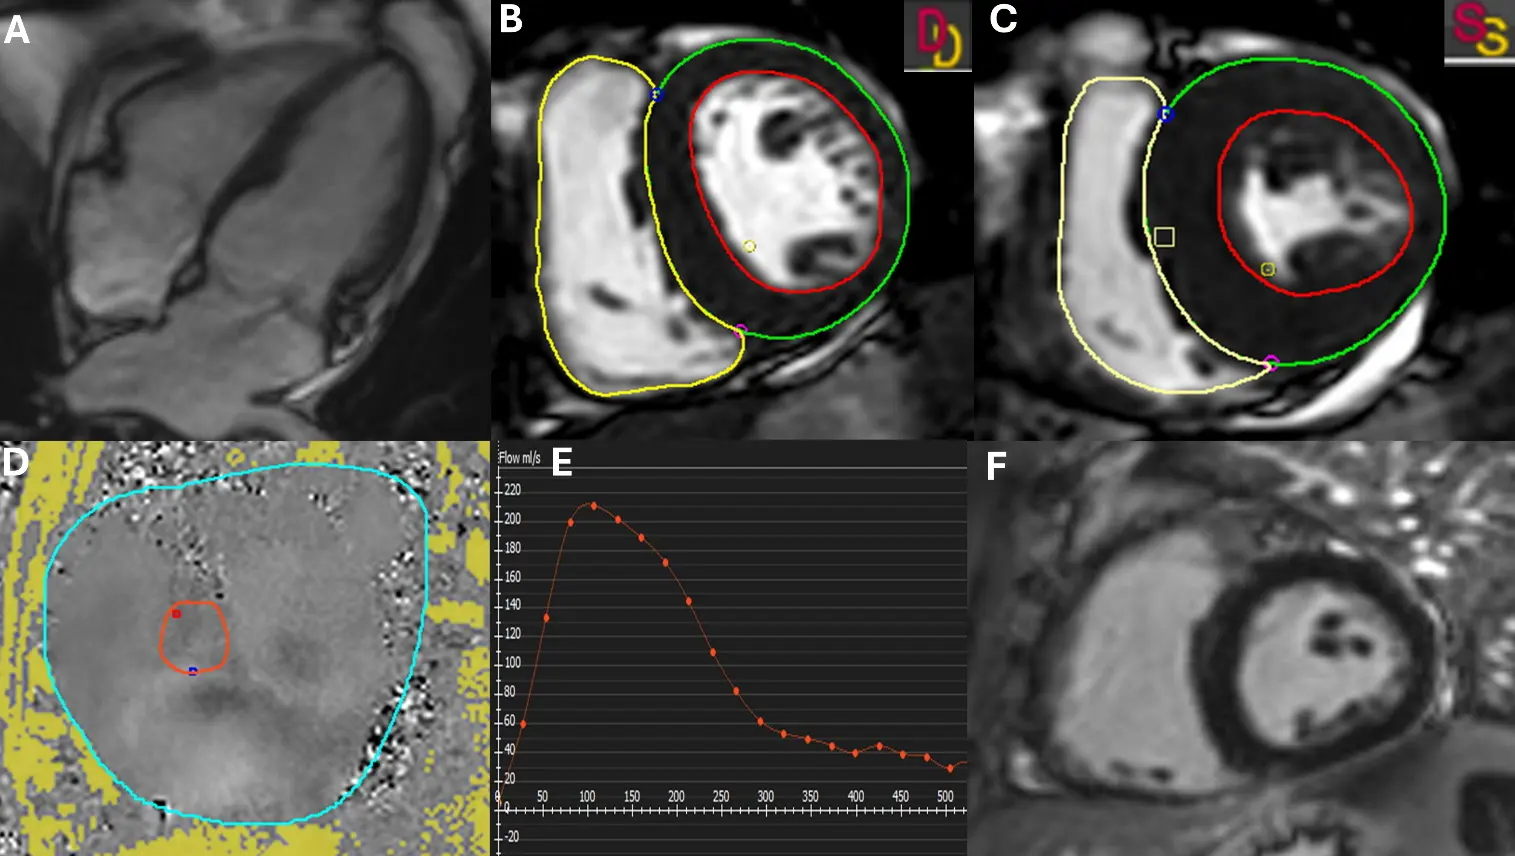

Cardiac magnetic resonance (CMR) imaging offers a comprehensive, high-resolution, and reproducible assessment of both cardiac chambers and the mitral valve apparatus, making it an invaluable tool for evaluating FMR (Figure 6) [88,89,90,91]. As the reference standard for quantifying left ventricular and atrial volumes, systolic function, and remodeling, CMR plays an increasingly central role in the diagnosis, risk stratification, and longitudinal monitoring of patients with FMR [37,68,92,93].

One of the key advantages of CMR is its ability to quantify mitral regurgitant volume and fraction with high accuracy and low operator dependency [88,90]. This is achieved by subtracting aortic forward stroke volume, measured via phase-contrast velocity mapping, from the total left ventricular stroke volume derived from cine images [38,88,94,95]. The resulting regurgitant fraction (≥35% is often considered severe) is highly reproducible and particularly helpful when echocardiographic assessments are technically limited or yield discordant findings [78,96]. These volumetric parameters provide a robust estimate of MR severity and reflect its hemodynamic burden over time, thereby aiding in therapeutic decision-making [78,96].

Figure 6. Cardiac Magnetic Resonance Evaluation of Mitral Regurgitation. (A) Cine four-chamber view demonstrating a systolic mitral regurgitant jet extending into the left atrium. (B,C) Short-axis stack at end-diastole (B) and end-systole (C) with manual contouring of the left ventricle to calculate end-diastolic volume (EDV), end-systolic volume (ESV), and stroke volume (SV). LV endocardial and epicardial contours are shown in red and green, respectively; the RV endocardial contour is shown in yellow. ED and ES frames are indicated (D = end-diastole; S = end-systole). (D) 2D phase-contrast flow imaging acquired at the sinotubular junction (STJ) for quantification of aortic forward flow. The aortic lumen ROI used for flow integration is outlined in red, and the reference/background (phase-offset correction) ROI is outlined in cyan. (E) Corresponding flow curve generated from (D) used to calculate regurgitant volume (RV = aortic flow − SV) and regurgitant fraction (RF = RV/SV). The orange curve/markers represent instantaneous aortic flow across the cardiac cycle (positive = forward flow). (F) Late gadolinium enhancement (LGE) imaging demonstrates no evidence of myocardial fibrosis or scar.